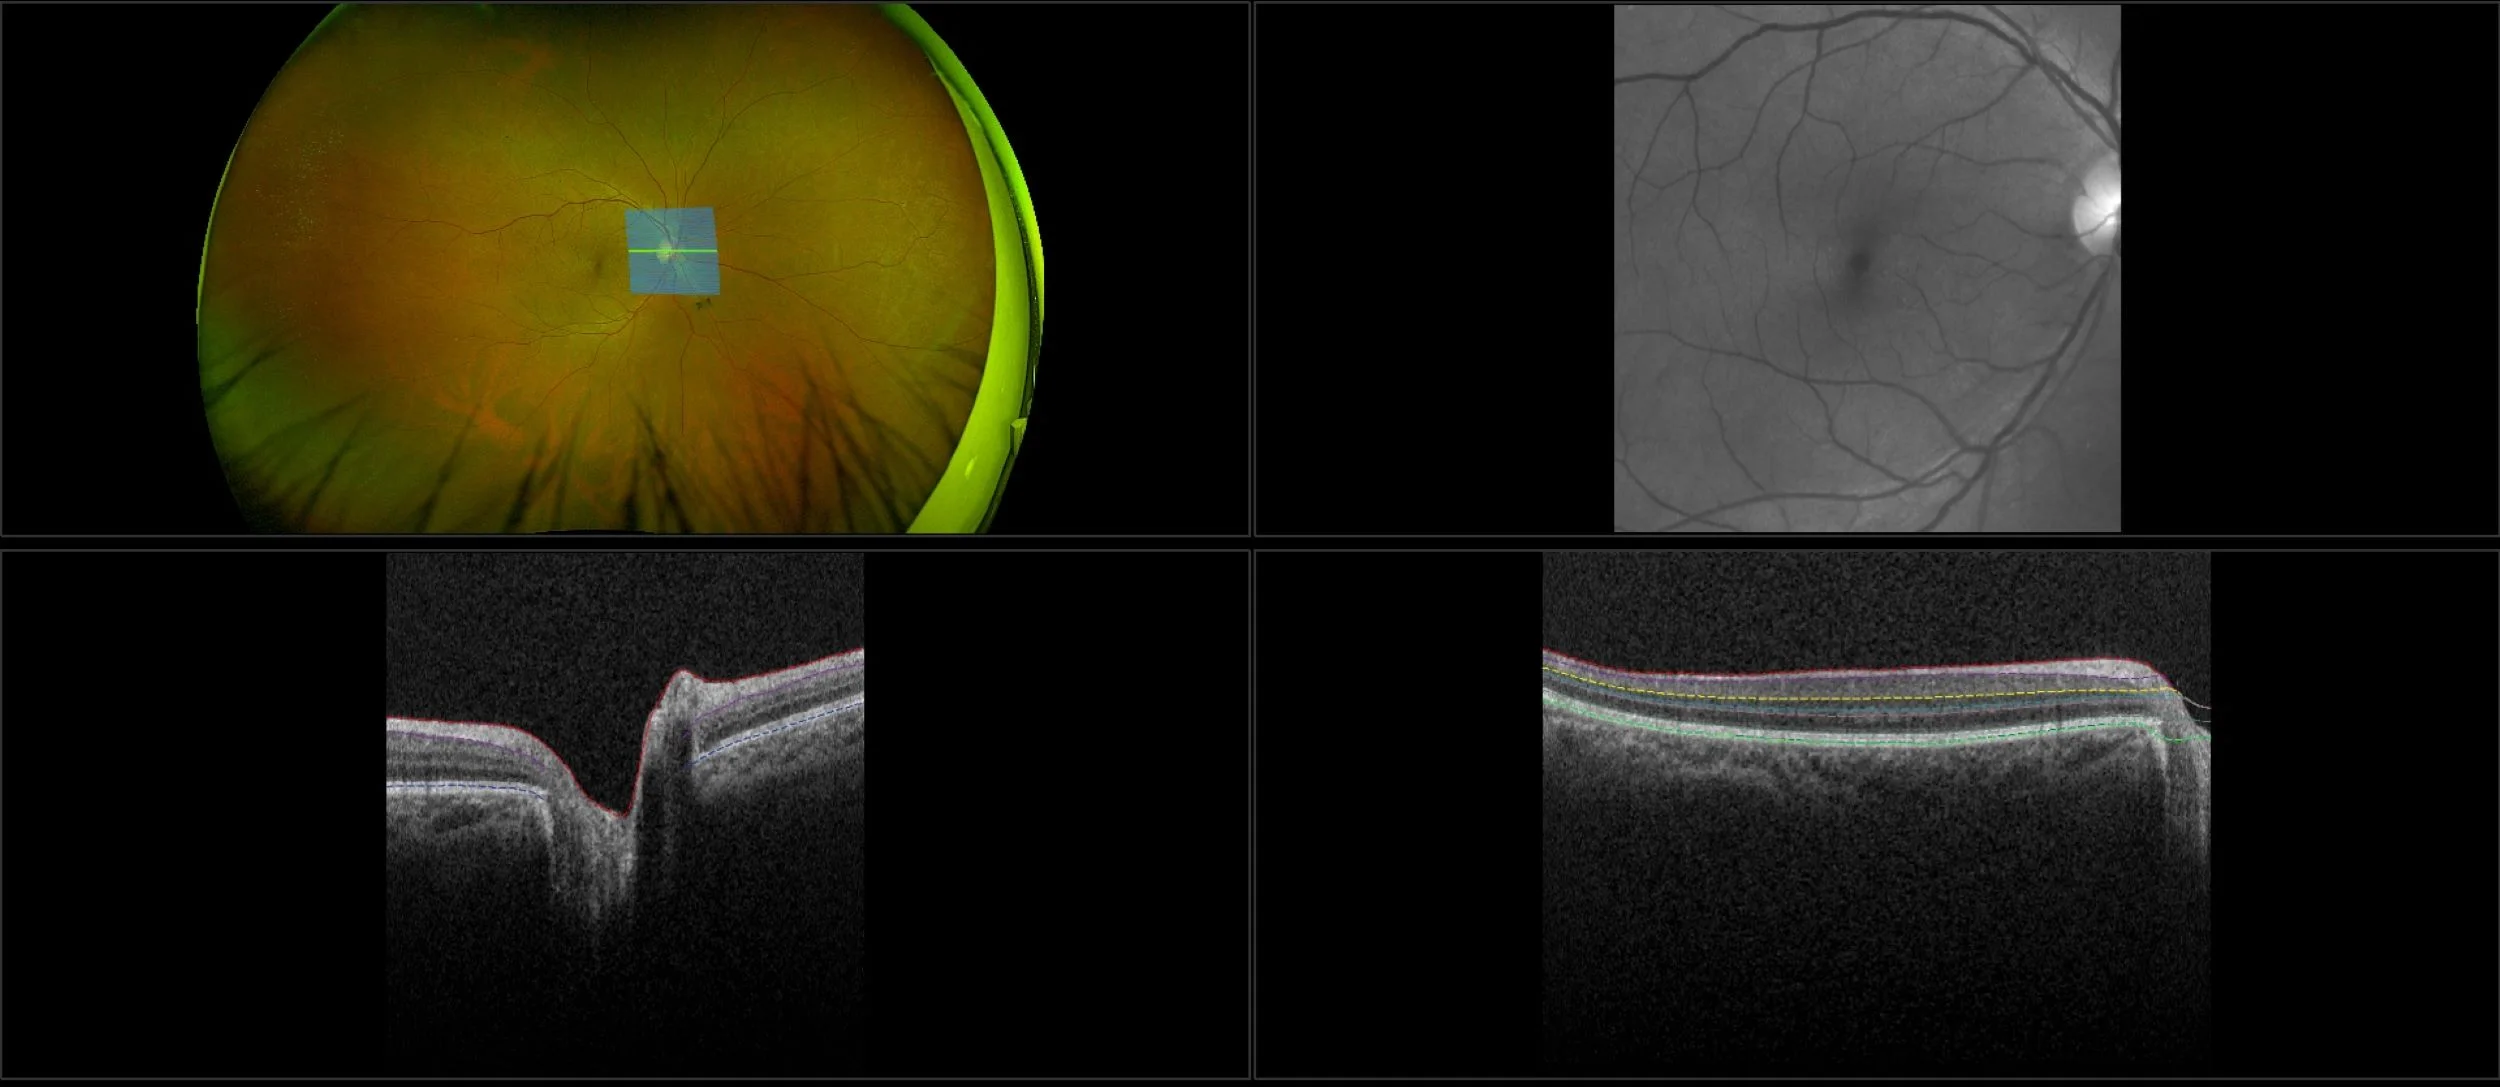

This material is designed as a searchable reference resource to support clinical decision-making. The information contained here should be used as general guidance when viewing optomap and OCT images from Optos devices. The differential diagnosis should be made under the direction of the responsible physician. These images were taken on the latest ultra-widefield optomap devices.

optomap Recognizing Pathology is searchable by pathology and/or optomap image modality. You may search by multiples of each selection. Each individual case is represented by the accompanying thumbnail image. Most cases include several different optomap image modalities. To view a full description of the case, please click on the thumbnail. Each image in the case will be made available through our OptosAdvance software which provides multi-dimensional visualization of digital images to aid in the analysis of anatomy and pathology. Support and pathology definitions can be found by selecting one of the buttons, above. Should you have questions, please complete the form below.